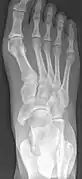

Radiological images

Accessory navicular bone may cause a continuous stretch and stress on the tibialis posterior tendon which can progress to chronic disabling pain and may cause tendon rupture or secondary flat foot deformity; when this occurs this condition is commonly known as accessory navicular syndrome.[4]

Other conditions which closely mimic the symptoms of an accessory navicular bone include plantar fasciitis, bunions and heel spurs.